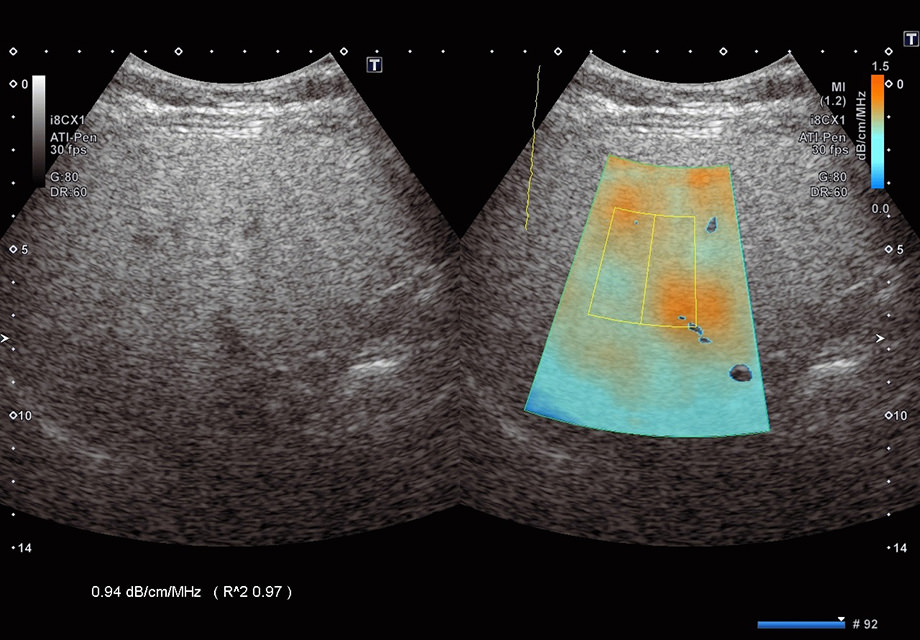

ATIによる脂肪肝診断の画像(指定された領域の超音波パルスが減少していく現象をカラーで表示。減っていく量を測定することで、数値化を実現)

(指定された領域の超音波パルスが減少していく現象をカラーで表示。減っていく量を測定することで、数値化を実現)

キヤノンが開発したATIは、患者さんの身体に放射された超音波パルスが生体組織を通過する際に、吸収や拡散などにより次第に減少していく現象(以下、減衰)に着目。正常な肝細胞と脂肪化した肝細胞の減衰量を測定し、数値化することに成功しました。